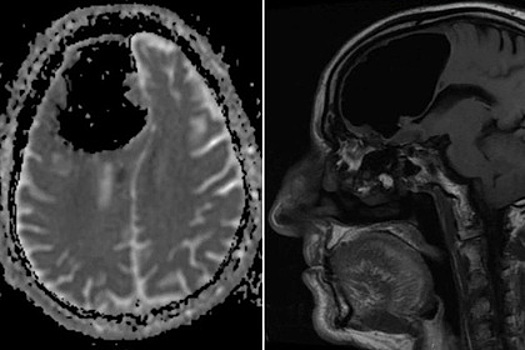

Отсутствие части головного мозга почти не повлияло на жизнь 84-летнего мужчины из Северной Ирландии. Об этом сообщает New York Post со ссылкой на научную работу, опубликованную в медицинском журнале BMJ Case Reports. Пациент обратился в больницу с жалобой на частые падения и ощущение неустойчивости, которое появилось у него несколько месяцев назад. Кроме того, он рассказал о слабости в конечностях левой стороны тела. В остальном его самочувствие было хорошим, мышление сохраняло ясность, нарушения речи или зрения отсутствовали. Компьютерная томография показала, что на месте правой лобной доли его мозга находится большая полость с воздухом, поперечник которой составляет девять сантиметров. При дополнительном обследовании на магнитно-резонансном томографе рядом обнаружилась крупная остеома — доброкачественная костная опухоль, развитие которой, по всей видимости, и привело к образованию полости. Кроме того, медики заметили нарушение кровоснабжения мозолистого тела — сплетения нервных волокон, соединяющих полушария головного мозга. Пациенту предложили операцию, во время которой будет проведена очистка заполненной воздухом полости и удалена опухоль. Мужчина оценил возможные последствия и отказался от хирургического вмешательства. После этого он выписался из больницы. В 2017 году сообщалось, что американские врачи обнаружили в мозге 27-летнего мужчины гигантскую арахноидальную кисту, которая сплющила правое полушарие головного мозга.